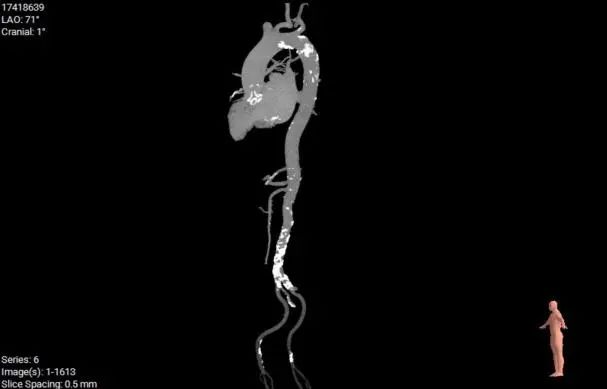

CT数据显示该患者为三叶瓣主动脉瓣。

主动脉瓣瓣环周长65.0mm,平均周长径 20.5mm,sov:25.7mm*27.1mm,瓣叶增厚,钙化主要分布于瓣叶,瓣环水平夹角51°。

外周血管及主动脉弓解剖

股动脉入路无迂曲,分叉高度可。髂总、腹主钙化分布。左侧血管平均最小内径6.0mm, 右侧血管平均最小内径6.0mm。

建议右侧股动脉为主入路,穿刺点附近少量钙化分布,建议避开钙化穿刺。